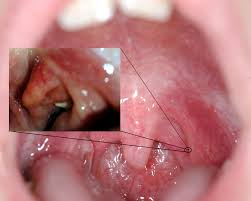

Cuando abres la boca lo suficiente y miras al espejo puedes ubicar las amígdalas en la parte posterior de la garganta. Tener una infección de garganta por estreptococos que no desaparece puede ser un signo de mononucleosis. Bolitas blancas en la garganta Las bolitas blancas en la garganta también llamadas tonsitolitos o pierdas amigdalinas son simplemente una liga de desechos como glóbulos blancos moco bacterias placas de calcio y comida que van desintegrando las bacterias y es lo que produce el olor desagradable de estos tonsitolitos.

Cuando los puntos blancos aparecen en las amígdalas pueden presentarse como manchas o estrías. La fatiga asociada con mono avanza gradualmente al igual que otros síntomas como dolor de garganta. Para realizar gárgaras con agua tibia y sal basta mezclar un vaso de.

También pueden contener pus. El síntoma más común que se observa es dolor de garganta. Las áreas blancas situadas en la garganta pueden indicar una serie de condiciones médicas Hablamos sobre las causas y tratamiento del dolor de garganta con manchas blancas Puede ser causada por una infección bacteriana como bacterias estreptocócicas o una infección viral Su médico puede diagnosticar la causa exacta de estos puntos blancos la fiebre y otras.

Pus en la garganta. Las bolitas blancas en la garganta conocidas con el nombre de cáseum o tonsiolitos son pequeñas partículas que se adhieren a las amígdalas debido a la acumulación de restos de comida y. Puedes notar manchas blancas o amarillas en la parte posterior de la garganta en tus amígdalas.

Gárgaras con agua tibia y sal o con enjuagues bucales. Como resultado se produce mal aliento dolor e inflamación leve de la garganta olor desagradable y un bulto blancuzco conocido como piedra tonsilar.